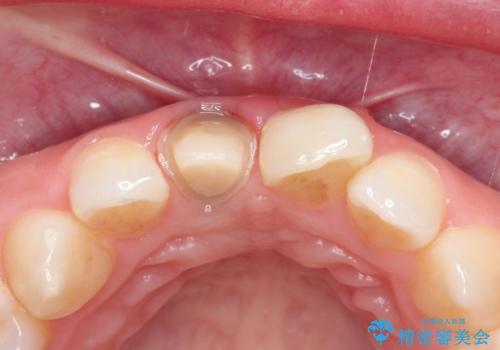

前歯の治療。再根管治療~セラミッククラウン

- 前歯の痛みを主訴に来院された患者様です。

再根管治療を行い、セラミックにて被せものを行いました。

根管治療では無菌的処置と拡大視野下による処置を行い成功率を高めた治療を行っております。